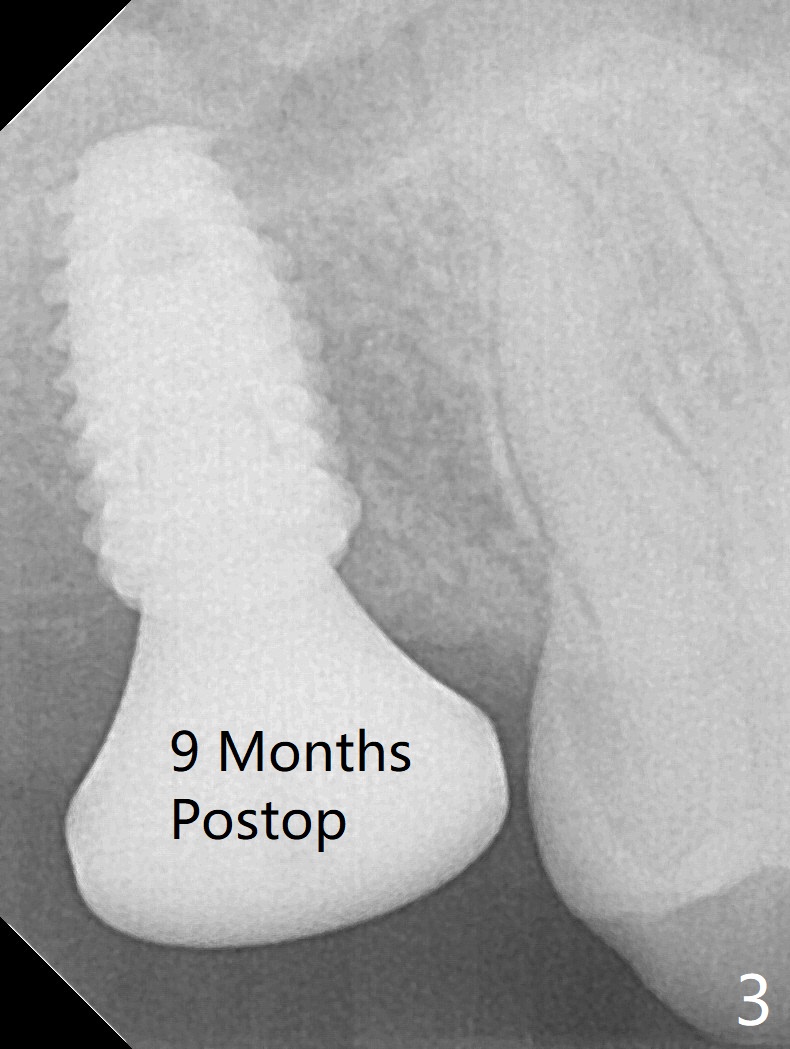

In spite of underprep (4.0x8.5 mm last drill), a 5x8.5 mm implant is placed at #2 with insertion torque ~ 15 Ncm (Fig.1). In addition to the large defect post implant removal with 4.5 month bone graft, he is a heavy gagger with limited mouth opening. Drill cylinders may not engage the metal sleeve precisely. A 5.5x4 mm healing abutment is placed with low emergency profile. The procedure, although difficult, finishes in a timely manner. Otherwise it would be a disaster for the patient and operator. PA taken 1 month postop shows slightly subcrestal placement (Fig.2). When a cemented abutment is placed 4 months postop, there is tenderness. In fact the implant is mobile. A 8x5 mm healing abutment is placed. Nine months postop, the implant remains slightly mobile (Fig.3); a healing screw is placed. The tooth #3 has sign and symptom of crack 13 months postop (Fig.4), related to root fracture of #19 (Fig.5, bruxism). In fact the tooth cracks nonsalvageable post RCT, 9 months post #2 healing screw, 21 months postop. Socket preservation will be carried out with sticky bone and PRF, while #2 implant will be uncovered, followed by placement of a short cemented abutment to hold periodontal dressing. Upper Molar Immediate Implant, Trajectory Xin Wei, DDS, PhD, MS 1st edition 11/27/2018, last revision 07/03/2021